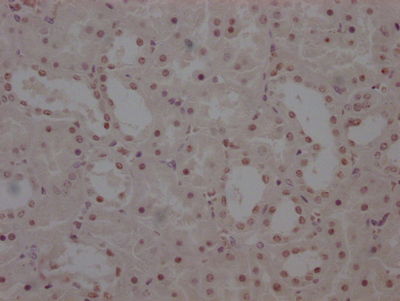

IHC image of CSB-PA896505DSR2HU diluted at 1:50 and staining in paraffin-embedded human colorectal cancer performed on a Leica BondTM system. After dewaxing and hydration, antigen retrieval was mediated by high pressure in a citrate buffer (pH 6.0). Section was blocked with 10% normal goat serum 30min at RT. Then primary antibody (1% BSA) was incubated at 4°C overnight. The primary is detected by a Goat anti-rabbit polymer IgG labeled by HRP and visualized using 0.05% DAB. Secondary antibody only control: uses 1% BSA instead of primary antibody